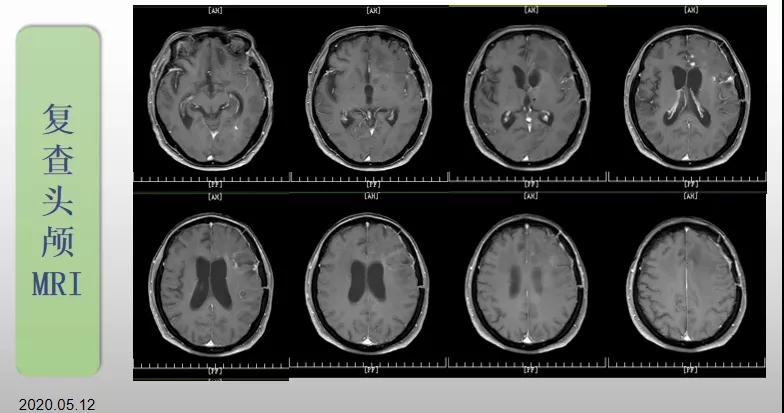

綜合治療 電場治療助70歲患者回歸正常生活

70歲的郝女士去年曾在外院查出“左額島葉”膠質(zhì)母細(xì)胞瘤(WHO Ⅳ級),并做了左側(cè)額島葉占位性病變切除術(shù)。術(shù)后進(jìn)行了同步放化療。由于治療條件有限,郝女士慕名來到我院就診。賀世明主任率領(lǐng)醫(yī)護(hù)團(tuán)隊(duì)立即為郝女士進(jìn)行了全面的檢查,決定為其進(jìn)行綜合治療 電場治療。經(jīng)過三個(gè)多月的綜合治療,患者復(fù)查頭顱MRI病變較前明顯縮小。出院時(shí),郝女士神志清醒,睡眠飲食正常,說話很流利。“我是躺著進(jìn)來的,現(xiàn)在不用人攙扶,自己就可以走出病房了?!焙屡坷t(yī)護(hù)人員的手說。